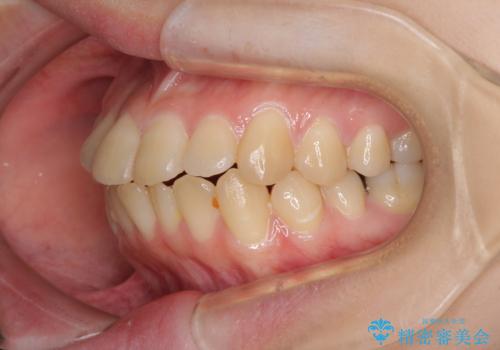

- 上下前歯が前方に飛び出しているとのことで来院された患者様です。

上下左右第一小臼歯4本を抜歯して、積極的に口元を引っ込めるよう、ワイヤー装置にて矯正治療を行うこととしました。

口元の突出感は著しく改善され、横顔の印象が大きく変化しました。